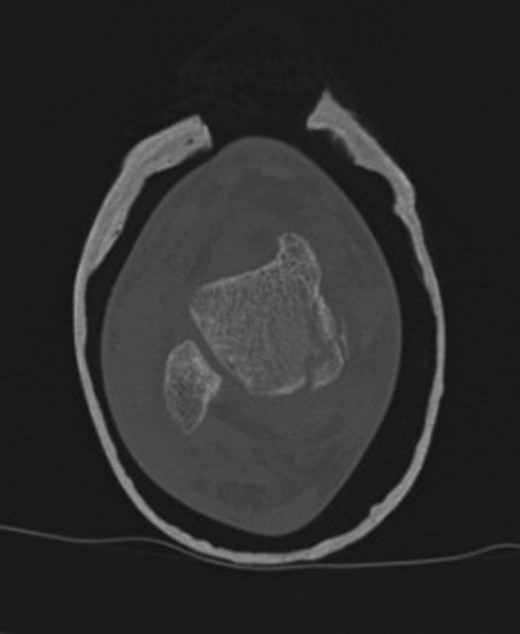

The patient subsequently underwent a manipulation under anaesthesia and POP application of his left distal tibia and right ankle to correct the talar displacement. Despite this, post-operative radiographs of the right ankle showed persistent widened medial tibio-talar joint, and the patient developed considerable right ankle pain and soft tissue swelling which did not correspond with the initial radiograph findings. Magnetic resonance imaging (MRI) of the right ankle joint was performed which revealed extensive marrow oedema through the medial malleolus epiphysis and the medial body of the talus. There was evidence of disruption of the medial cortex of the talus which explained the widened medial tibio-talar joint (Fig. 2). No disruptions of the epiphyseal plates or ligamentous structures were identified. The injury around the tibio-talar joint was identified as an undisplaced fracture through the postero-medial talus with a corresponding ‘kissing’-type lesion of the inner surface of the medial malleolus with gross soft tissue oedema. In view of the overlooked skeletal injury, a further computer tomography (CT) scan of the ankle joint was performed which confirmed a fragmented undisplaced fracture of the postero-medial aspect of the talus, with the anterior subtalar joint remaining intact and an undisplaced fracture through the medial malleolus (Fig. 3).

Right ankle CT axial view demonstrates undisplaced compression fracture of the medial body of the talus.

At 12 weeks follow-up, the patient was weight bearing comfortably with near full range of movement. A repeat CT and MRI scan showed no evidence of displacement of the fracture fragments with good evidence of talus fracture healing. MRI revealed reduction in bone marrow signal changes with no evidence of subchondral collapse (Figs 4 and 5).

12-week follow-up CT axial view of the talus confirms no further displacement of the fracture nor any evidence of osteonecrosis. There is radiological evidence of callus bridging the fracture site.